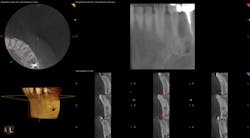

To determine whether tooth No. 21 or No. 22 was the issue, two periapical radiographs were taken. However, the results were inconclusive (figures 2–4). With clinical testing and 2-D radiographs providing no smoking gun, it was decided to use limited field-of-view CBCT (Carestream Dental CS 9000C 3D) on the region. CBCT revealed that tooth No. 22 was abscessed and a fair amount of the apical bone was completely gone (figures 5 and 6). In fact, since the time the pain began and when the patient presented at the practice, the tooth had abscessed at an alarming rate and was now considered an emergency situation.

Figure 6: CBCT showing a single view of the periapical lesion in the lower right of the screenshot